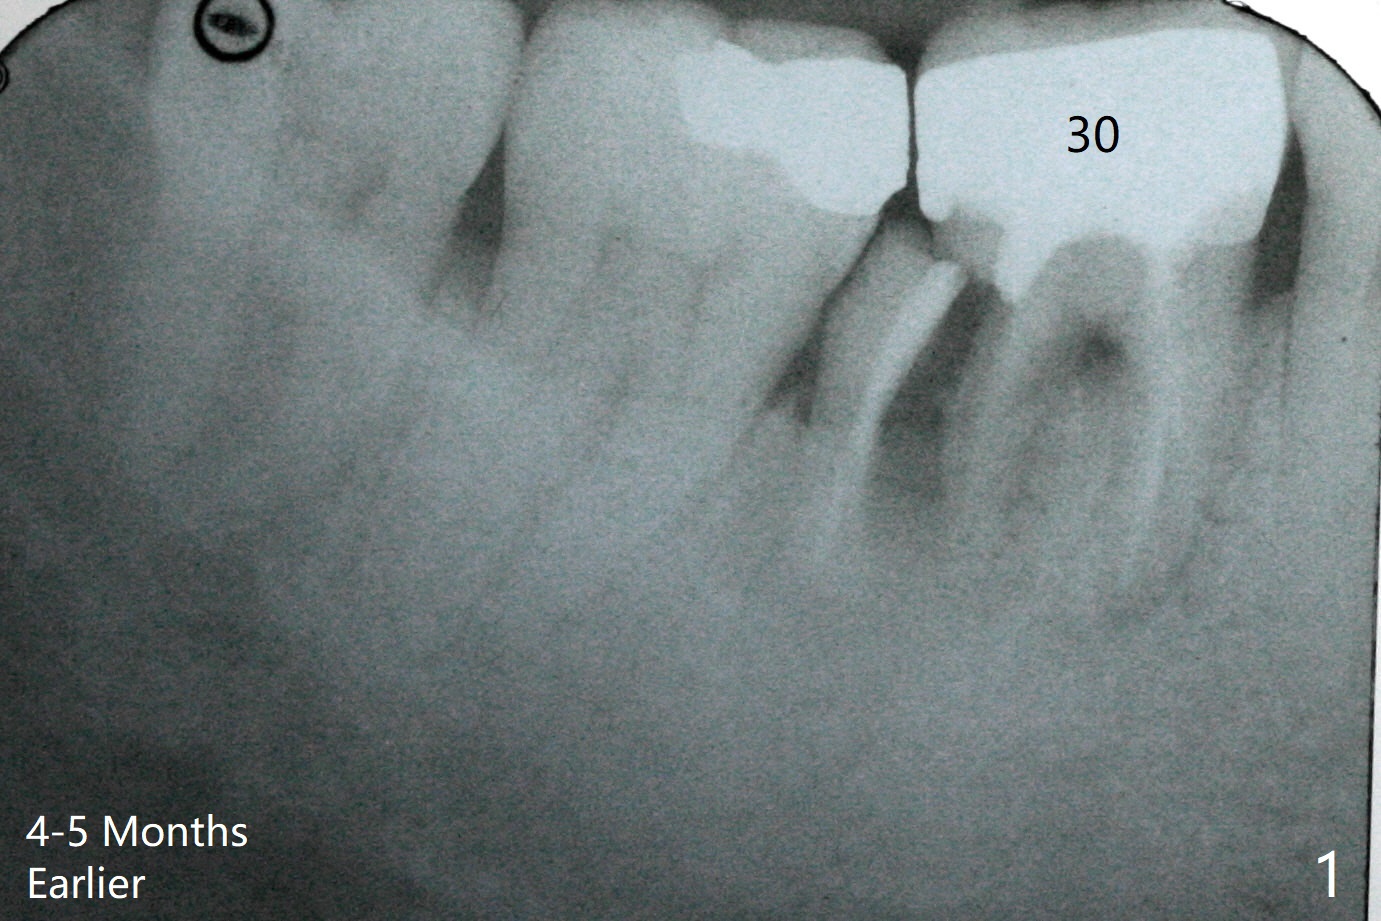

A 66-year-old woman loses a lot of bone at #30 in 4-5 months (Fig.1,2). There is severe buccal swelling, suggesting loss of the buccal plate and easy collapse of the gingiva after bone graft. In addition to an immediate provisional, periodontal dressing will be applied for support and seal. To prevent abutment screw loosening, guide will be used for implant placement in the most ideal trajectory (Fig.4). A tissue-level implant will provide with more security in prevention of screw loosening (Fig.5). If immediate implant is impossible, bone graft will be placed. Four months later, retake 5x5 cm CT for lab to determine the fitness of the guide.